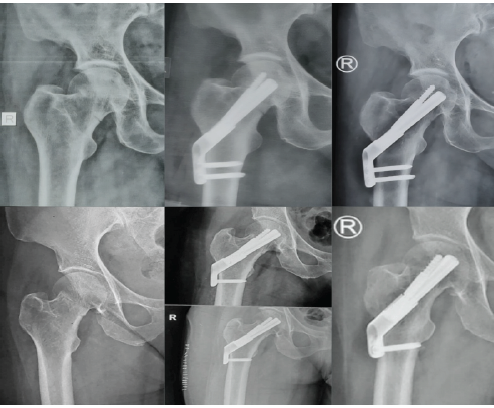

A 66-year-old female presented with a valgus-impacted Garden’s type I, Pauwel’s type I femoral neck fracture after a low-energy fall. Fixation was done in situ with the FNS device, applying mild compression and without any reduction maneuver. The blade and anti-rotation screw were positioned centrally with adequate tip-apex distance, and bi-cortical distal locking screws were used. By 3 months, radiographs showed complete bony union, and the patient returned to full function (Fig. 1). The good outcome could be attributed to the stable fracture pattern, early intervention, and favorable implant positioning.

Figure 1: Top left: pre-operative radiograph of Case 1; top center: immediate post-operative radiograph; top right: post-operative radiograph at 3 months. Bottom left – pre-operative AP radiograph of Case 2; bottom center – immediate post-operative radiograph; bottom right: post-operative radiographs at 3 months.

Case 2

A 64-year-old female sustained a valgus-impacted Garden’s type I, Pauwel’s type I fracture. Similar to the previous case, the fracture was fixed in situ with compression using the FNS device, with central implant placement and bi-cortical distal locking. At 3 months, complete union was observed, and functional recovery was achieved (Fig. 1). The predictable healing here may reflect the inherent stability of valgus-impacted fractures combined with timely fixation.